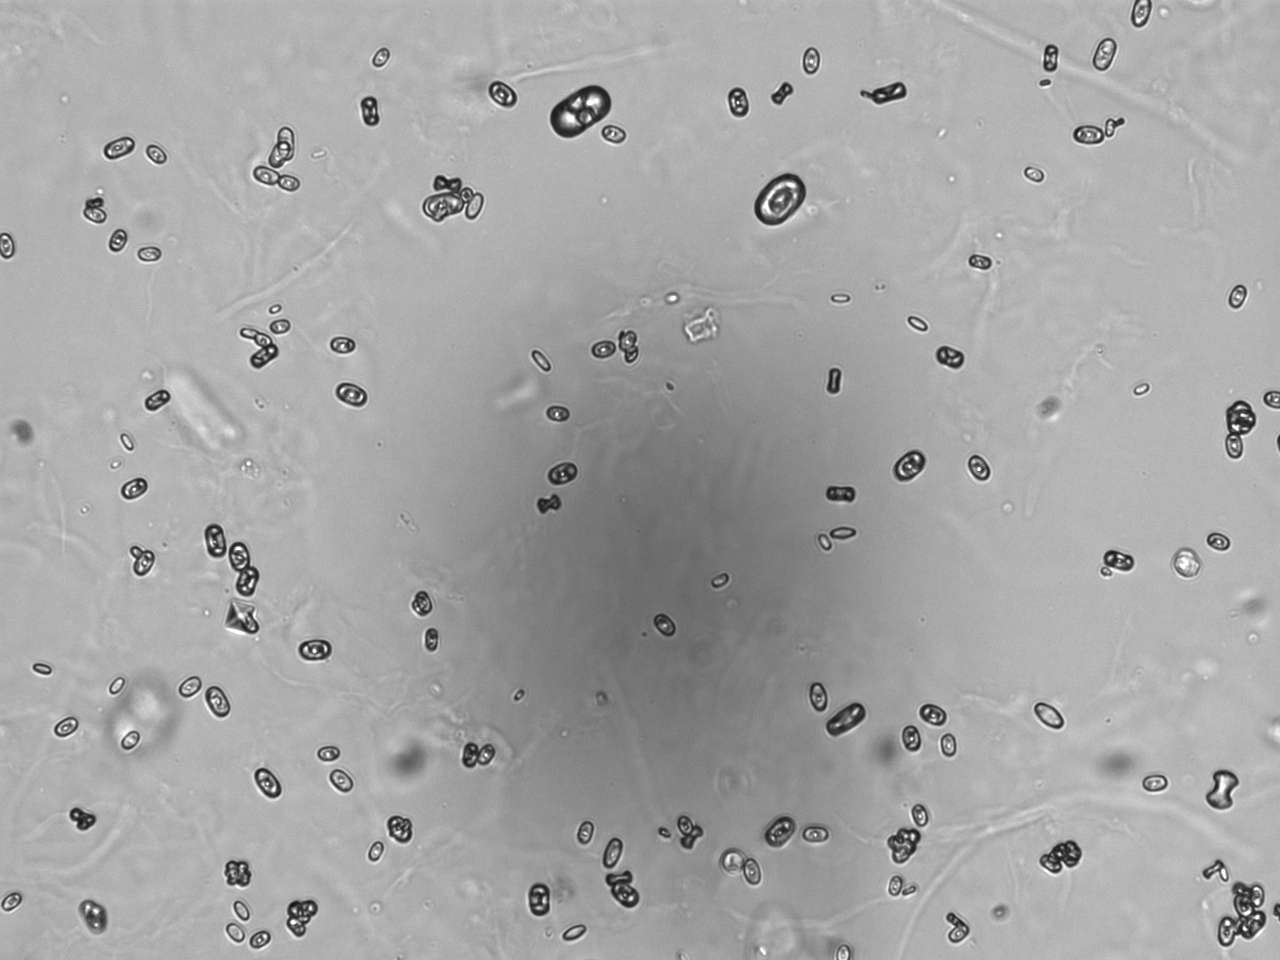

Urin-Feature: CaOxalateMonohyd